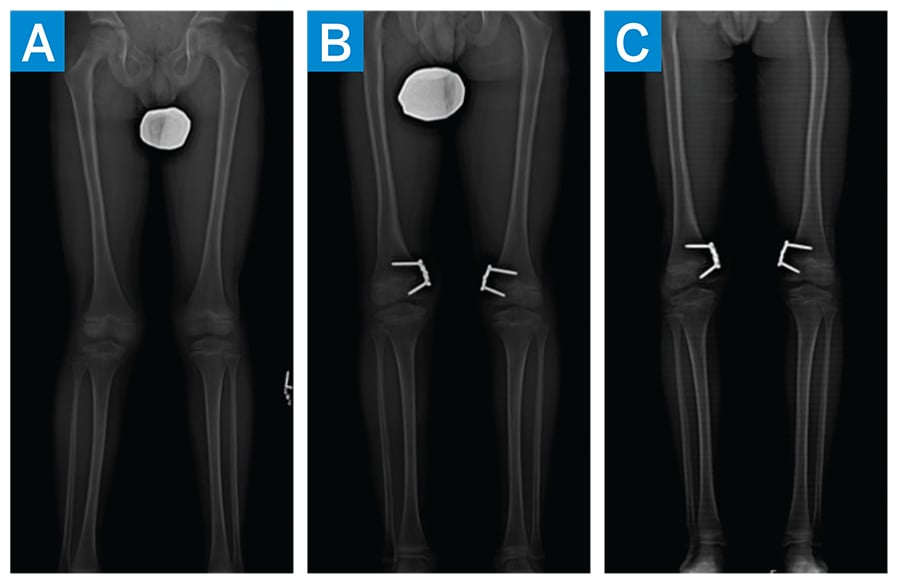

Patellar instability, represented in about 3% of all knee injuries, occurs most often in people ages 10 to 16 [1]. Genu valgum increases the risk for patellar dislocation and therefore may need to be addressed in skeletally immature patients with patellar instability [2]. Our patient presented with lower limb axis showing valgus alignment, with the mechanical axis alignment off by 15 mm on the right limb and 8 mm on the left limb. Implant-mediated guided growth was used to correct the malalignment. Bilateral plates were left in place for an additional 2 months after achieving correction in order to achieve a desirable amount of overcorrection (Fig. 4) [3]. Such overcorrection decreases the risk of rebound valgus that could lead to future patellar instability.

Figure 4: Standing EOS images demonstrating progression of lower extremity alignment. (a) Preoperative (b) 8 months postoperative (c) 10 months postoperative